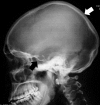

Summary: A 20-year-old man with an 8-year history of progressive enlargement of his hands and feet, coarsening facial features, painful joints and thickened, oily skin was referred for investigation of acromegaly. On examination, the subject was of normal height and weight. He had markedly increased skin thickness around the forehead, eyelids and scalp with redundant skin folds. Bilateral painful knee swelling was accompanied by enlargement of the extremities, and his fingers were markedly clubbed. Routine hematological, biochemical and hormonal blood tests, including GH and IGF-1 were normal. The clinical picture suggested primary hypertrophic osteoarthropathy (PHOA) rather than acromegaly and radiological studies were supportive of this, demonstrating increased subperiosteal bone formation and increased bone density and cortical thickening. There was widespread joint disease, with narrowing of joint spaces, whereas the knees demonstrated effusions and calcification. A skull X-ray revealed calvarial hyperostosis and a normal sellar outline. Family history was negative. Genetic studies were performed on peripheral blood leukocyte DNA for mutations in the two genes associated with PHOA, 15-hydroxyprostaglandin dehydrogenase (HPGD; OMIM: 601688) and solute carrier organic anion transporter family member 2A1 (SLCO2A1; OMIM: 601460). The sequence of HPGD was normal, whereas the subject was homozygous for a novel pathological variant in SLCO2A1, c.830delT, that predicted a frameshift and early protein truncation (p.Phe277Serfs*8). PHOA, also known as pachydermoperiostosis, is a rare entity caused by abnormal prostaglandin E2 metabolism, and both HPGD and SLCO2A1 are necessary for normal prostaglandin E2 handling. High prostaglandin levels lead to bone formation and resorption and connective tissue inflammation causing arthropathy, in addition to soft tissue swelling.